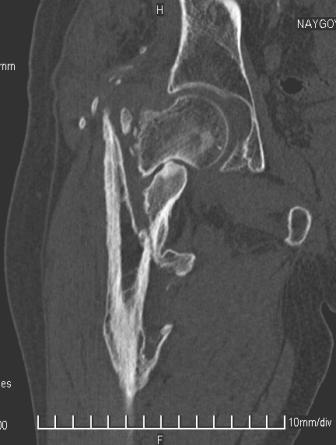

[Ortho] Сросшийся со смещением чрез-подвертельный перелом

Имя     : уменьш (6).jpg

Тип     : image/jpeg

Размер  : 16464 байтов

Url     : http://weborto.net:8080/pipermail/ortho/attachments/20091031/f055a08c/attachment-0006.jpg